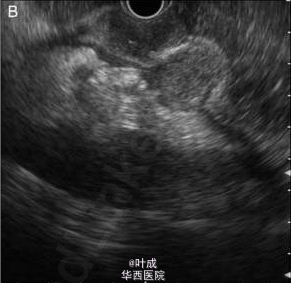

来自印度海得拉巴亚洲胃肠病研究所的 Ramchandani 等报道了一个罕见的胃结核病例,发表在最近的 Gut 杂志上。患者,男性,47 岁,消化不良、上腹部不适 2 个月,伴有体重减轻约 4kg,无消化道出血,无发热、咳嗽。既往否认传染病、手术史。体格检查无特殊。实验室检查示:血红蛋白 114g/L,血沉增快 54mm/h。心电图、胸片无异常。 胃镜示:胃体处可见多个粘膜下肿物 (图 A),贲门、胃窦粘膜正常。血中嗜铬粒蛋白 A 和尿液中 5 羟基吲哚乙酸水平正常。行超声内镜检查(图 B) 并于引导下行肿物穿刺,病理示可见肉芽肿。